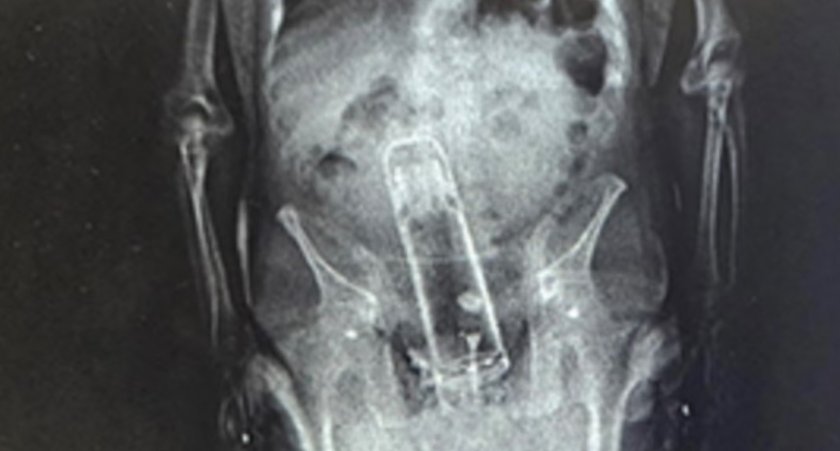

Американски пандизчия беше задържан при опит да внесе зад решетките не опиати, оръжие или даже мобилен телефон, а... еднолитров термос. За задачата 51-годишният Уолтър Фримайър е заврял съда в ануса си, твърди шерифското бюро във Флорида.

Полицаите разкрили метамфетамини у мъжагата, само че огромната изненада пристигнала при прегледа след ареста. Докторите открили голямо непознато тяло в дупарата на нещастника.

Според полицията Фримайър е бил закаран в болница, а предметът е отхвърлен. Няма никакви данни за какво, по дяволите, арестантът си е мушнал термоса откъм гърба.